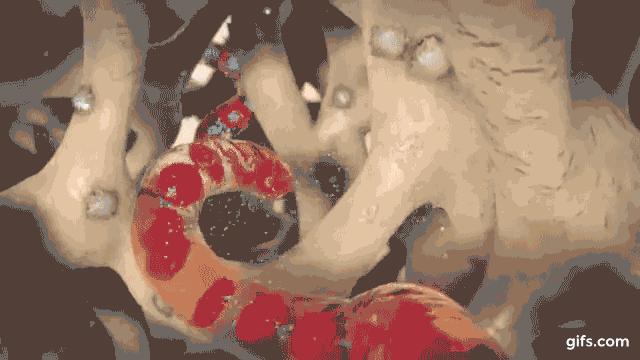

这时候调控磷的内分泌器官---甲状旁腺就不乐意了。甲状旁腺不是甲状腺,虽然两者位置挨在一块,名字只差一个字,但是功能完全不同,甲状腺负责神经、智力发育、生长、能量这块。甲状旁腺(下图中四颗“小豆豆”似的东西)是专门负责“钙、磷”平衡的老大。如果你是老大,你看到手底下的兵在体内到处乱窜,是不是也不乐意?